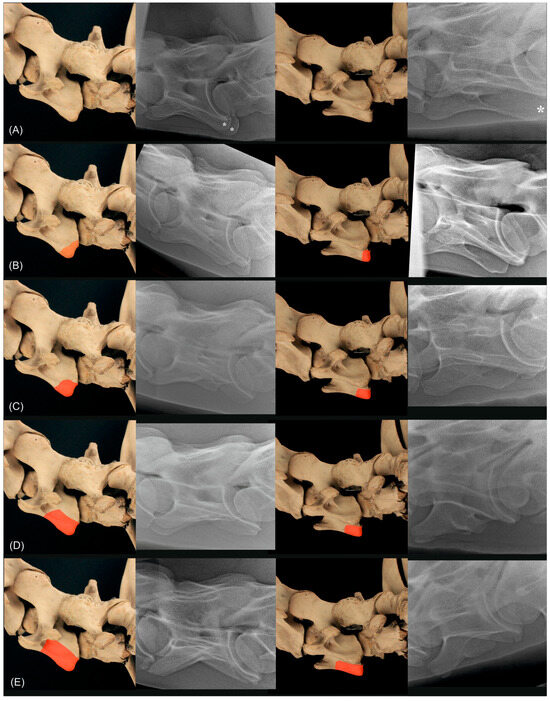

2.3. Radiographic Method

2.4. Classification System

| Grade | Morphologic Appearance |

|---|---|

| Normal | Normal lamina |

| 1 | 1–25% aplasia of the ventral lamina |

| 2 | 26–50% aplasia of the ventral lamina |

| 3 | 51–75% aplasia of the ventral lamina |

| 4 | 76–100% aplasia of the ventral lamina |

| Normal | 75% of the height of the cranial aspect of the vertebral body of T1 |

| 1 | 74–51% of the height of the cranial aspect of the vertebral body of T1 |

| 2 | 50–30% of the height of the cranial aspect of the vertebral body of T1 |

| 3 | <30% of the height of the cranial aspect of the vertebral body of T1 |

| 4 | absent |

| Normal | 75% of the height of the cranial aspect of the body of T1 |

| 1—large rudimentary | 74–51% of the height of the cranial aspect of the body of T1 |

| 2—medium rudimentary | 50–30% of the height of the cranial aspect of the body of T1 |

| 3—small rudimentary | <30% of the height of the cranial aspect of the body of T1 |